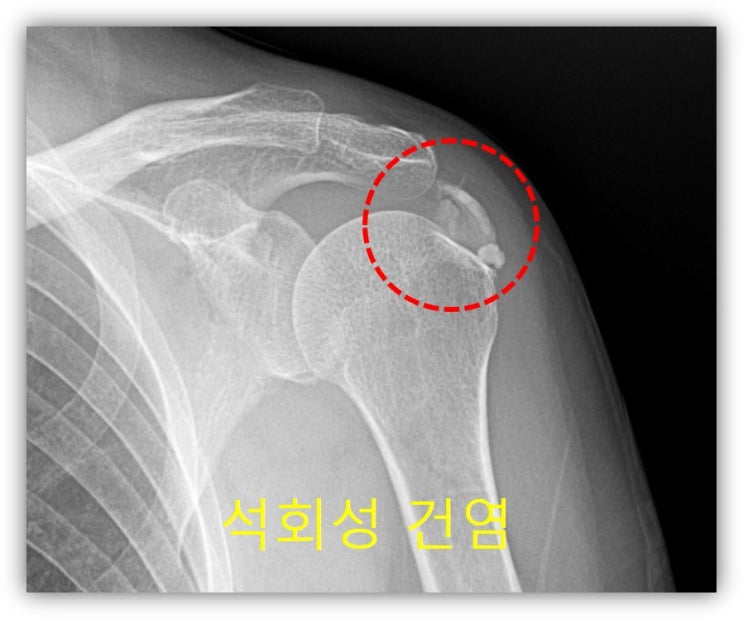

안녕하세요. 이번에는 석회성 건염으로 병원을 내원하신 환자에게 뉴핌스 치료를 한 사례를 보여드리겠습니다. 66세 여자 환자 분으로 6개월간 좌측 어깨 통증이 심하게 있으셨고 타 병원에서 아플때 주사만 맞았던 환자 였습니다. 최근들어 통증이 너무 심해져서 내월 2일 전에도 타병원에서 주사를 맞았으나 전혀 호전이 안되어 저한테 내원하였습니다. 통증이 너무 심하여 이학적 검사를 하지 못했고 x-ray 상 어마어마한 석회성 건염이 관찰되었습니다.

석회가 아주 큰 경우, 그리고 오래된 경우 회전근개의 손상이 있을 가능성이 있어 MRI 검사도 시행하였습니다.